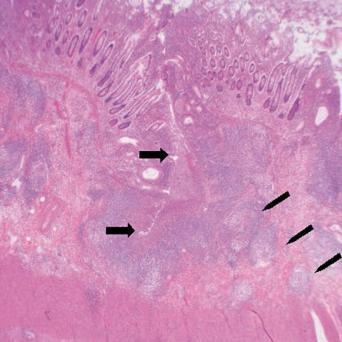

La stéatopathie métabolique est devenue la première cause de maladie chronique du foie. Le risque principal est la fibrose, qui, lorsqu’elle est sévère, peut évoluer vers une cirrhose et un carcinome hépatocellulaire. Qui faut-il dépister en soins primaires et comment interpréter les résultats ? Quelles options thérapeutiques ont fait leurs preuves ? Que peut-on attendre des nouvelles molécules ? Le point avec le Pr Stanislas Pol, hépatologue, hôpital Cochin, Paris.